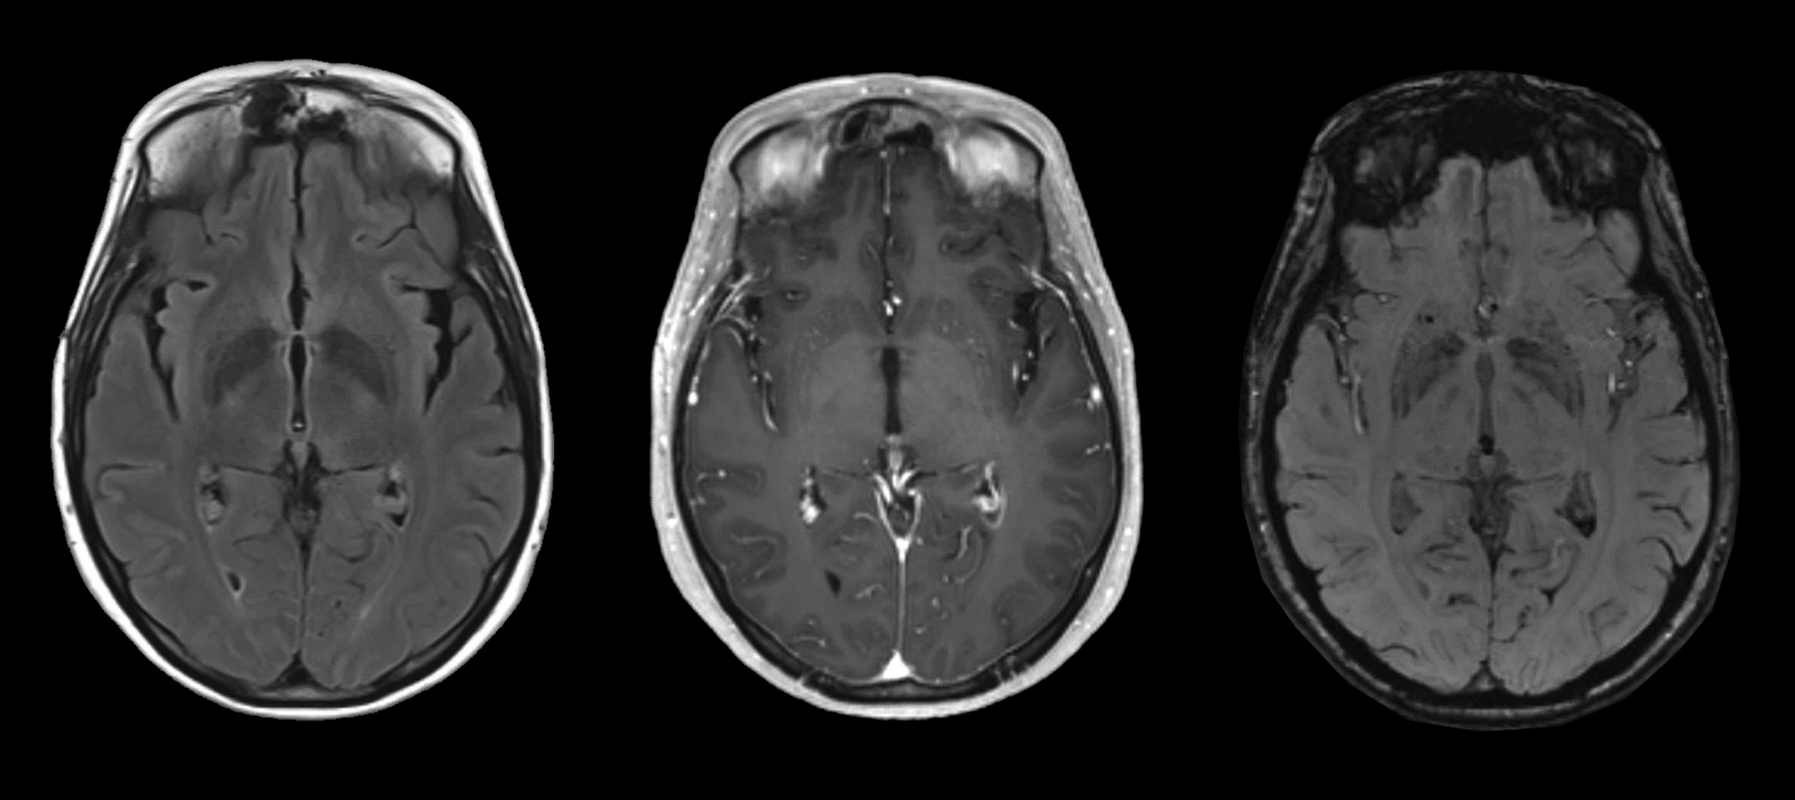

MRI sequences part 1 MRI sequences part 2 MRI sequences part 3

Her neuroimaging is clearly abnormal. Let's start with her MRI brain w/w/o contrast from one month ago. You can see the T2/FLAIR, T1 +C, and SWI sequences for three key slices. What do you notice?

She has some subtle FLAIR hyperintensities around the lining of her occipital horns. Minimal FLAIR hyperintensity in the right frontal region, though that's from her prior metastasis that was resected. What's notable is the absence of significant FLAIR hyperintensity around her right frontal lobe site, left frontal ependymal nodule, or even ventricular lining. There's no clear vasogenic edema or evidence of transependymal flow.

There's subtle contrast enhancement of the ventricles, shown here around the occipital horns and trigone, as well as of the ependymal nodule. What about the SWI sequences?

Other than the expected post-surgical changes, the left frontal ependymal nodule is hypointense. There's hypointense signal within the cerebellar foliae and fourth ventricle as well. While you'd normally think of subarachnoid hemorrhaging, in the context of her known metastatic melanoma, this all represents leptomeningeal spread of her cancer.